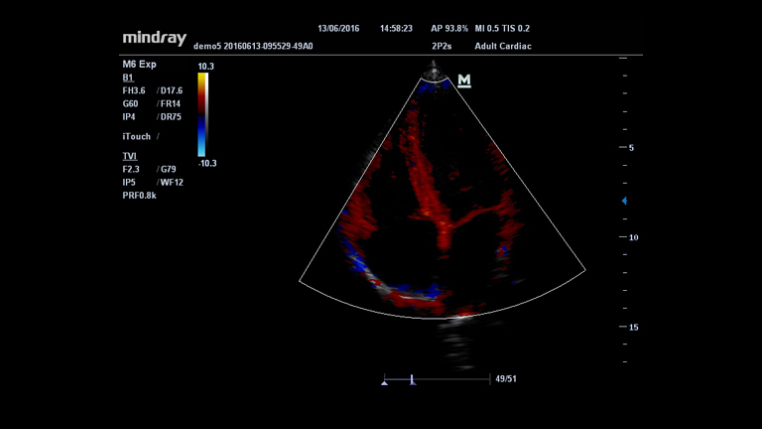

Toma de im√°genes de contraste UWN (Ultra-Wideband Non-linear, Ultra-ancho de banda no lineal)

La toma de imágenes de contraste UWN permite al M6 detectar y utilizar la segunda armónica y las se?ales fundamentales no lineales, lo que permite generar imágenes con mejoras significativas.

- Se?al menor m√°s sensible, dosis de agente reducida

- Duración de agente más larga con requisito MI más bajo